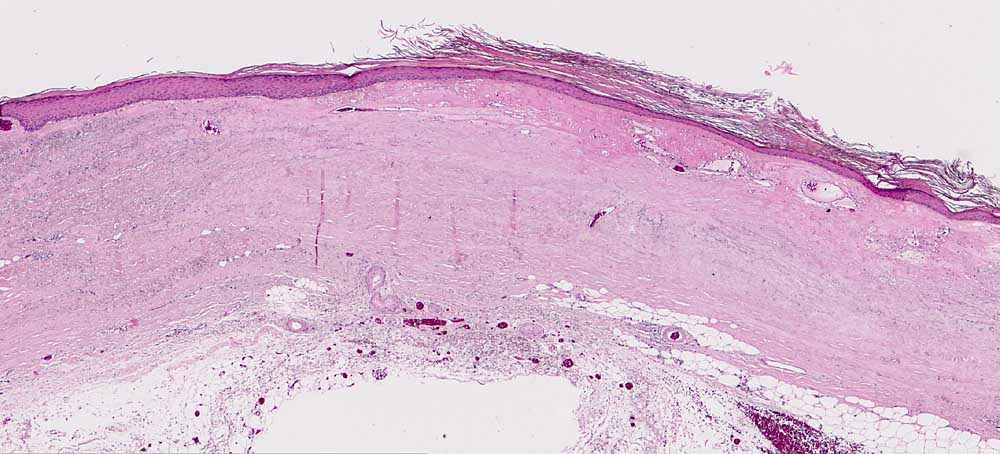

PathoPic ID 6861 - Chronische Radiodermatitis

Chronische Radiodermatitis

Therapiefolgen

Haut, Rumpf

Haut

Herdförmige Hyperkeratose. Vollständige Atrophie der Adnexe. Dermale Sklerose und fokale

Elastose.

Teleangiektasien. Fibröse

Wandverdickung der Blutgefässe.

Fraktionierte Bestrahlung vor mehreren Jahren.

Histologie

25